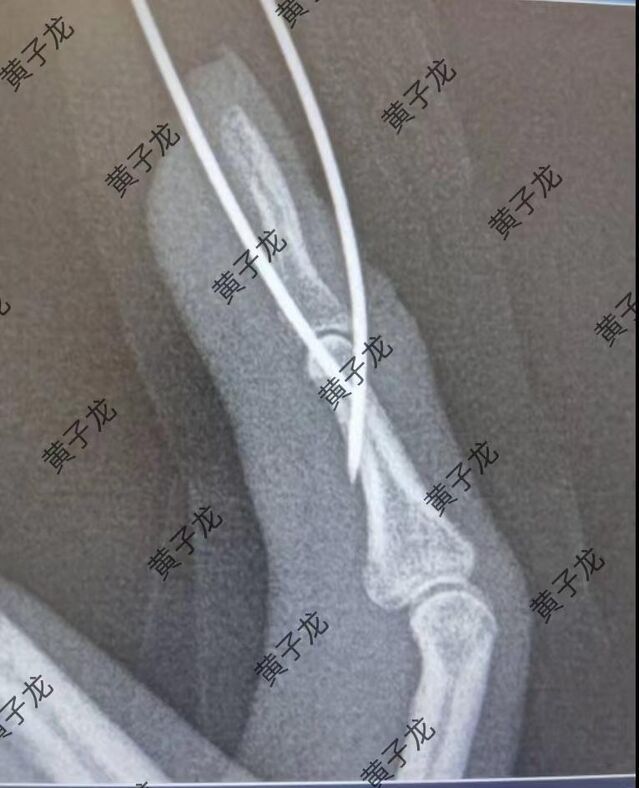

[修复重建] 小指伸肌腱止点撕脱性陈旧性骨折

陈旧性骨折近一个月,来我院就诊。我采用切开复位阻挡法,效果满意! 图片1.png 图片2.png 图片3.png 图片4.png 图片5.png 图片6.png 图片7.png

术后6周